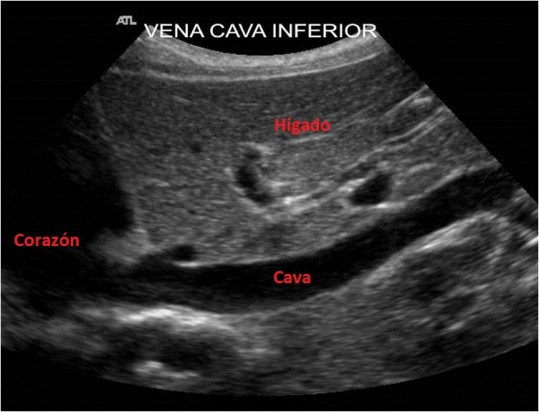

Cava Inferior

La Vena Cava Inferior entra en el corazón con sangre «sucia» y es ese instante el que tenemos que fotografiar. Ecográficamente es anecoica, alargada, ligeramente abombada y físicamente es depresible por compresión. En este corte podemos ver la llegada de la Vena Suprahepática Izquierda que en algunos casos podemos sacarla incluida en este corte, pero yo he preferido estudiarla en el contexto del estudio ecográfico de las Suprahepáticas. Podemos observar que esta vena está en íntimo contacto con el Hígado.

The Vena Cava Inferior enters the heart with «dirty» blood and that is the moment that we have to photograph. Ultrasound is anechoic, elongated, slightly bulging and physically depressed by compression. In this section we can see the arrival of the Left Suprahepatic Vein that in some cases we can remove it included in this section, but I have preferred to study it in the context of the ultrasound study of the Suprahepatic. We can see that this vein is in intimate contact with the Liver. We will also observe in transverse, but as I said before, for the protocol we are left with these two images in longitudinal. They are easy to get, sometimes we will achieve it with deep inspiration from the patient, but other times, and especially the Cava, we will see it much better in expiration.